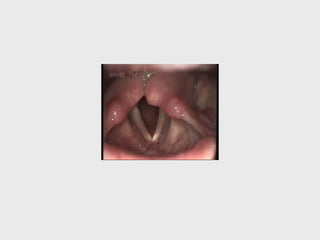

BILATERAL RLNP

( ABDUCTOR PARALYSIS)

DEFN: condition in which al the intrinsic

muscles of larynx are paralysed

bilaterally. except cricothyroid

C/F :

- Acute in onset

- dyspnea

- stridor

• - becomes worse during exertion and

infection

• voice : good

• position of vc: median / paramedian